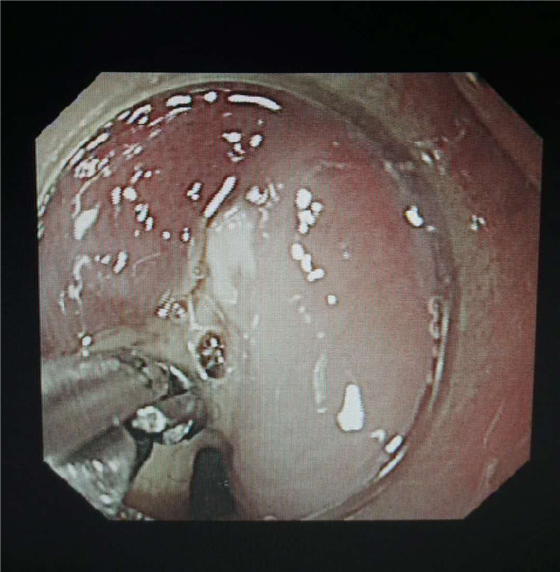

近日,一位中年妇女在家中误食鱼刺后3天来我院耳鼻喉科就诊,耳鼻喉科予以胸部CT检查,发现鱼刺已经卡在食管上段,患者随即转入我院消化内科。消化内科同患者及家属充分沟通后,拟胃镜下取出术异物。胃镜进入食管后,发现鱼刺两端已经深深的卡在食管上,可见脓液从鱼刺旁流出。邓佳佳医师和柯星梅主管护师,在科主任刘东升主任医师的指导下,用异物钳小心夹住鱼刺上端,缓慢的拔出拉入胃镜前端的透明帽内,随胃镜一起把鱼刺安全取出。由于患者鱼刺嵌顿时间较长,及时安排患者住院治疗,目前患者已治愈出院。